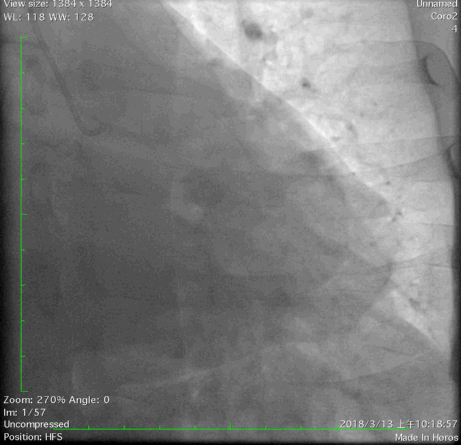

2018年3月13日外院行造影检查示左优势,LAD发出后闭塞,LCX优势型,远端可见与LAD远端形成心外膜侧支,OM1闭塞,RCA闭塞。当地尝试开通RCA和LAD失败,经我院心内、外科联合讨论后,拟心内科介入开通LAD闭塞。

冠脉造影: